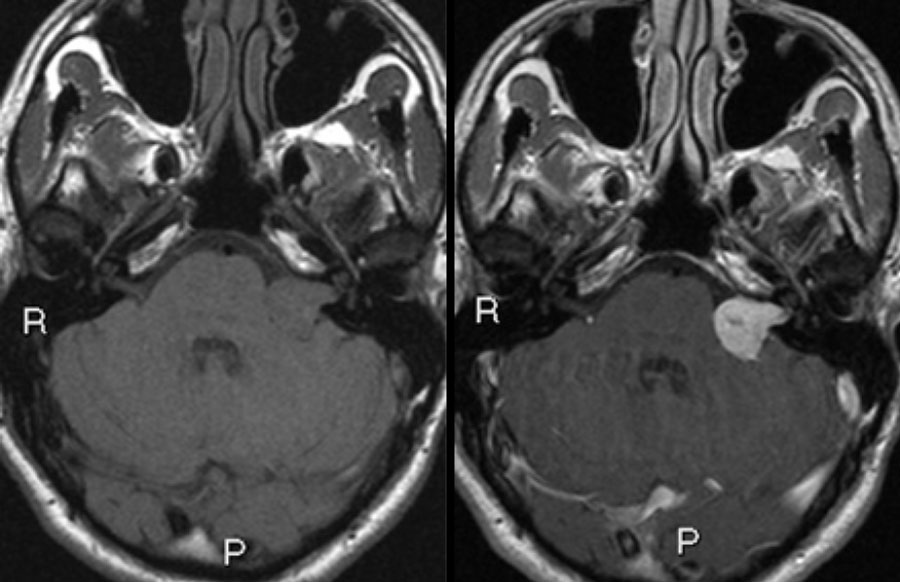

SLAB 3D MRI with contrast, performed three years after diagnosis Can You Work After Mri With Contrast These dyes are generally safe drugs that cause certain blood vessels and tissues to show more clearly on the images taken during your scan. It’s important to stay as still as possible to ensure the images are clear. Contrast injections may cause side effects like mild rashes and hives, but it is also possible for a person to have a. Can You Work After Mri With Contrast.

Brain MRI with contrast eight months after discharge T1 with contrast Can You Work After Mri With Contrast Mri without contrast means we do not give the gadolinium based contrast through an iv. Contrast materials can help highlight areas of interest in mri scans. Your technologist will do everything they can to help you get accurate. After your magnetic resonance imaging (mri) with contrast media. Your physician might recommend an mri with contrast. Sometimes when undergoing an mri. Can You Work After Mri With Contrast.

Repeat MRI with contrast T1. MRI of the brain axial with contrast T1 Can You Work After Mri With Contrast It’s important to stay as still as possible to ensure the images are clear. Contrast dyes can either be ingested or injected through an iv. This allows the radiologist to see certain internal structures in more detail. You will be given the. Contrast injections may cause side effects like mild rashes and hives, but it is also possible for a. Can You Work After Mri With Contrast.

MR images of Cases 1, 3, and 4. The MRI with contrast enhancement shows Can You Work After Mri With Contrast Sometimes when undergoing an mri scan, you’ll receive a contrast solution, which is a liquid given orally or through an iv. You will be given the. After you arrive for your mri, the technologist will help you get positioned on a moveable exam table. It’s important to stay as still as possible to ensure the images are clear. Contrast materials. Can You Work After Mri With Contrast.

Postoperative MRI with contrast Postoperative T1 MRI with contrast Can You Work After Mri With Contrast Sometimes when undergoing an mri scan, you’ll receive a contrast solution, which is a liquid given orally or through an iv. Contrast injections may cause side effects like mild rashes and hives, but it is also possible for a person to have a serious. This means we do the mri without contrast. This allows the radiologist to see certain internal. Can You Work After Mri With Contrast.

Repeat MRI with contrast T1. MRI of the brain axial with contrast T1 Can You Work After Mri With Contrast Your physician might recommend an mri with contrast. This allows the radiologist to see certain internal structures in more detail. This means we do the mri without contrast. You will be given the. Your technologist will do everything they can to help you get accurate. Contrast injections may cause side effects like mild rashes and hives, but it is also. Can You Work After Mri With Contrast.